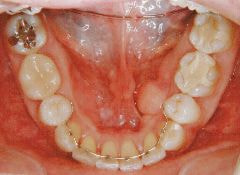

治療例2 (補綴処置+矯正)